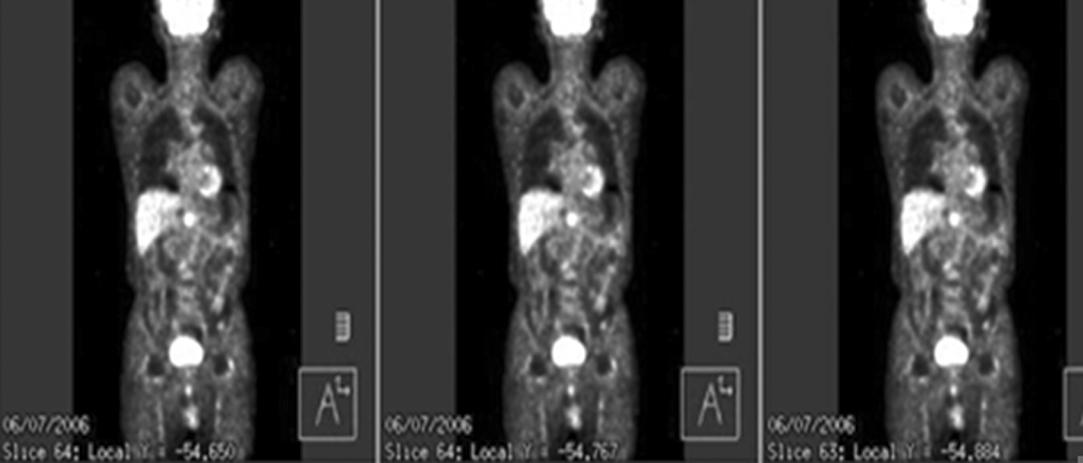

Fig. 3. 18F-fluorodeoxyglucose (FDG) PET/CT scan at 3.5 months after radiotherapy. The increased 18F-FDG uptake on the enlarged node was near completely disappeared.

The response of radiotherapy was remarkable and on 18F-FDG PET/CT scan, there was no increased FDG uptake on the metastatic node at 3.5 month from the end of radiotherapy (Fig. 3) and on abdomen CT scan, it was completely disappeared at 12 months from radiotherapy. There was no evidence of recurrence until 3.5 years follow-up (Fig. 4).